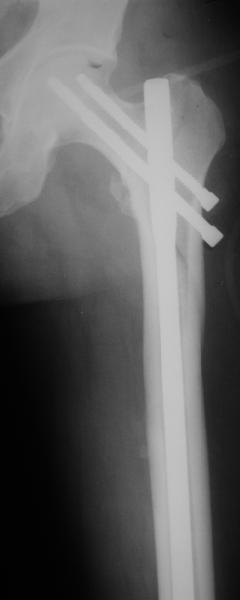

Да, сейчас это и у нас самый напрашивающийся выбор. Сделали гвоздем ChM, картинки в приложении.

У молодых реконструкционный гвоздь самое то. При остеопорозе надо что-то помассивнее.